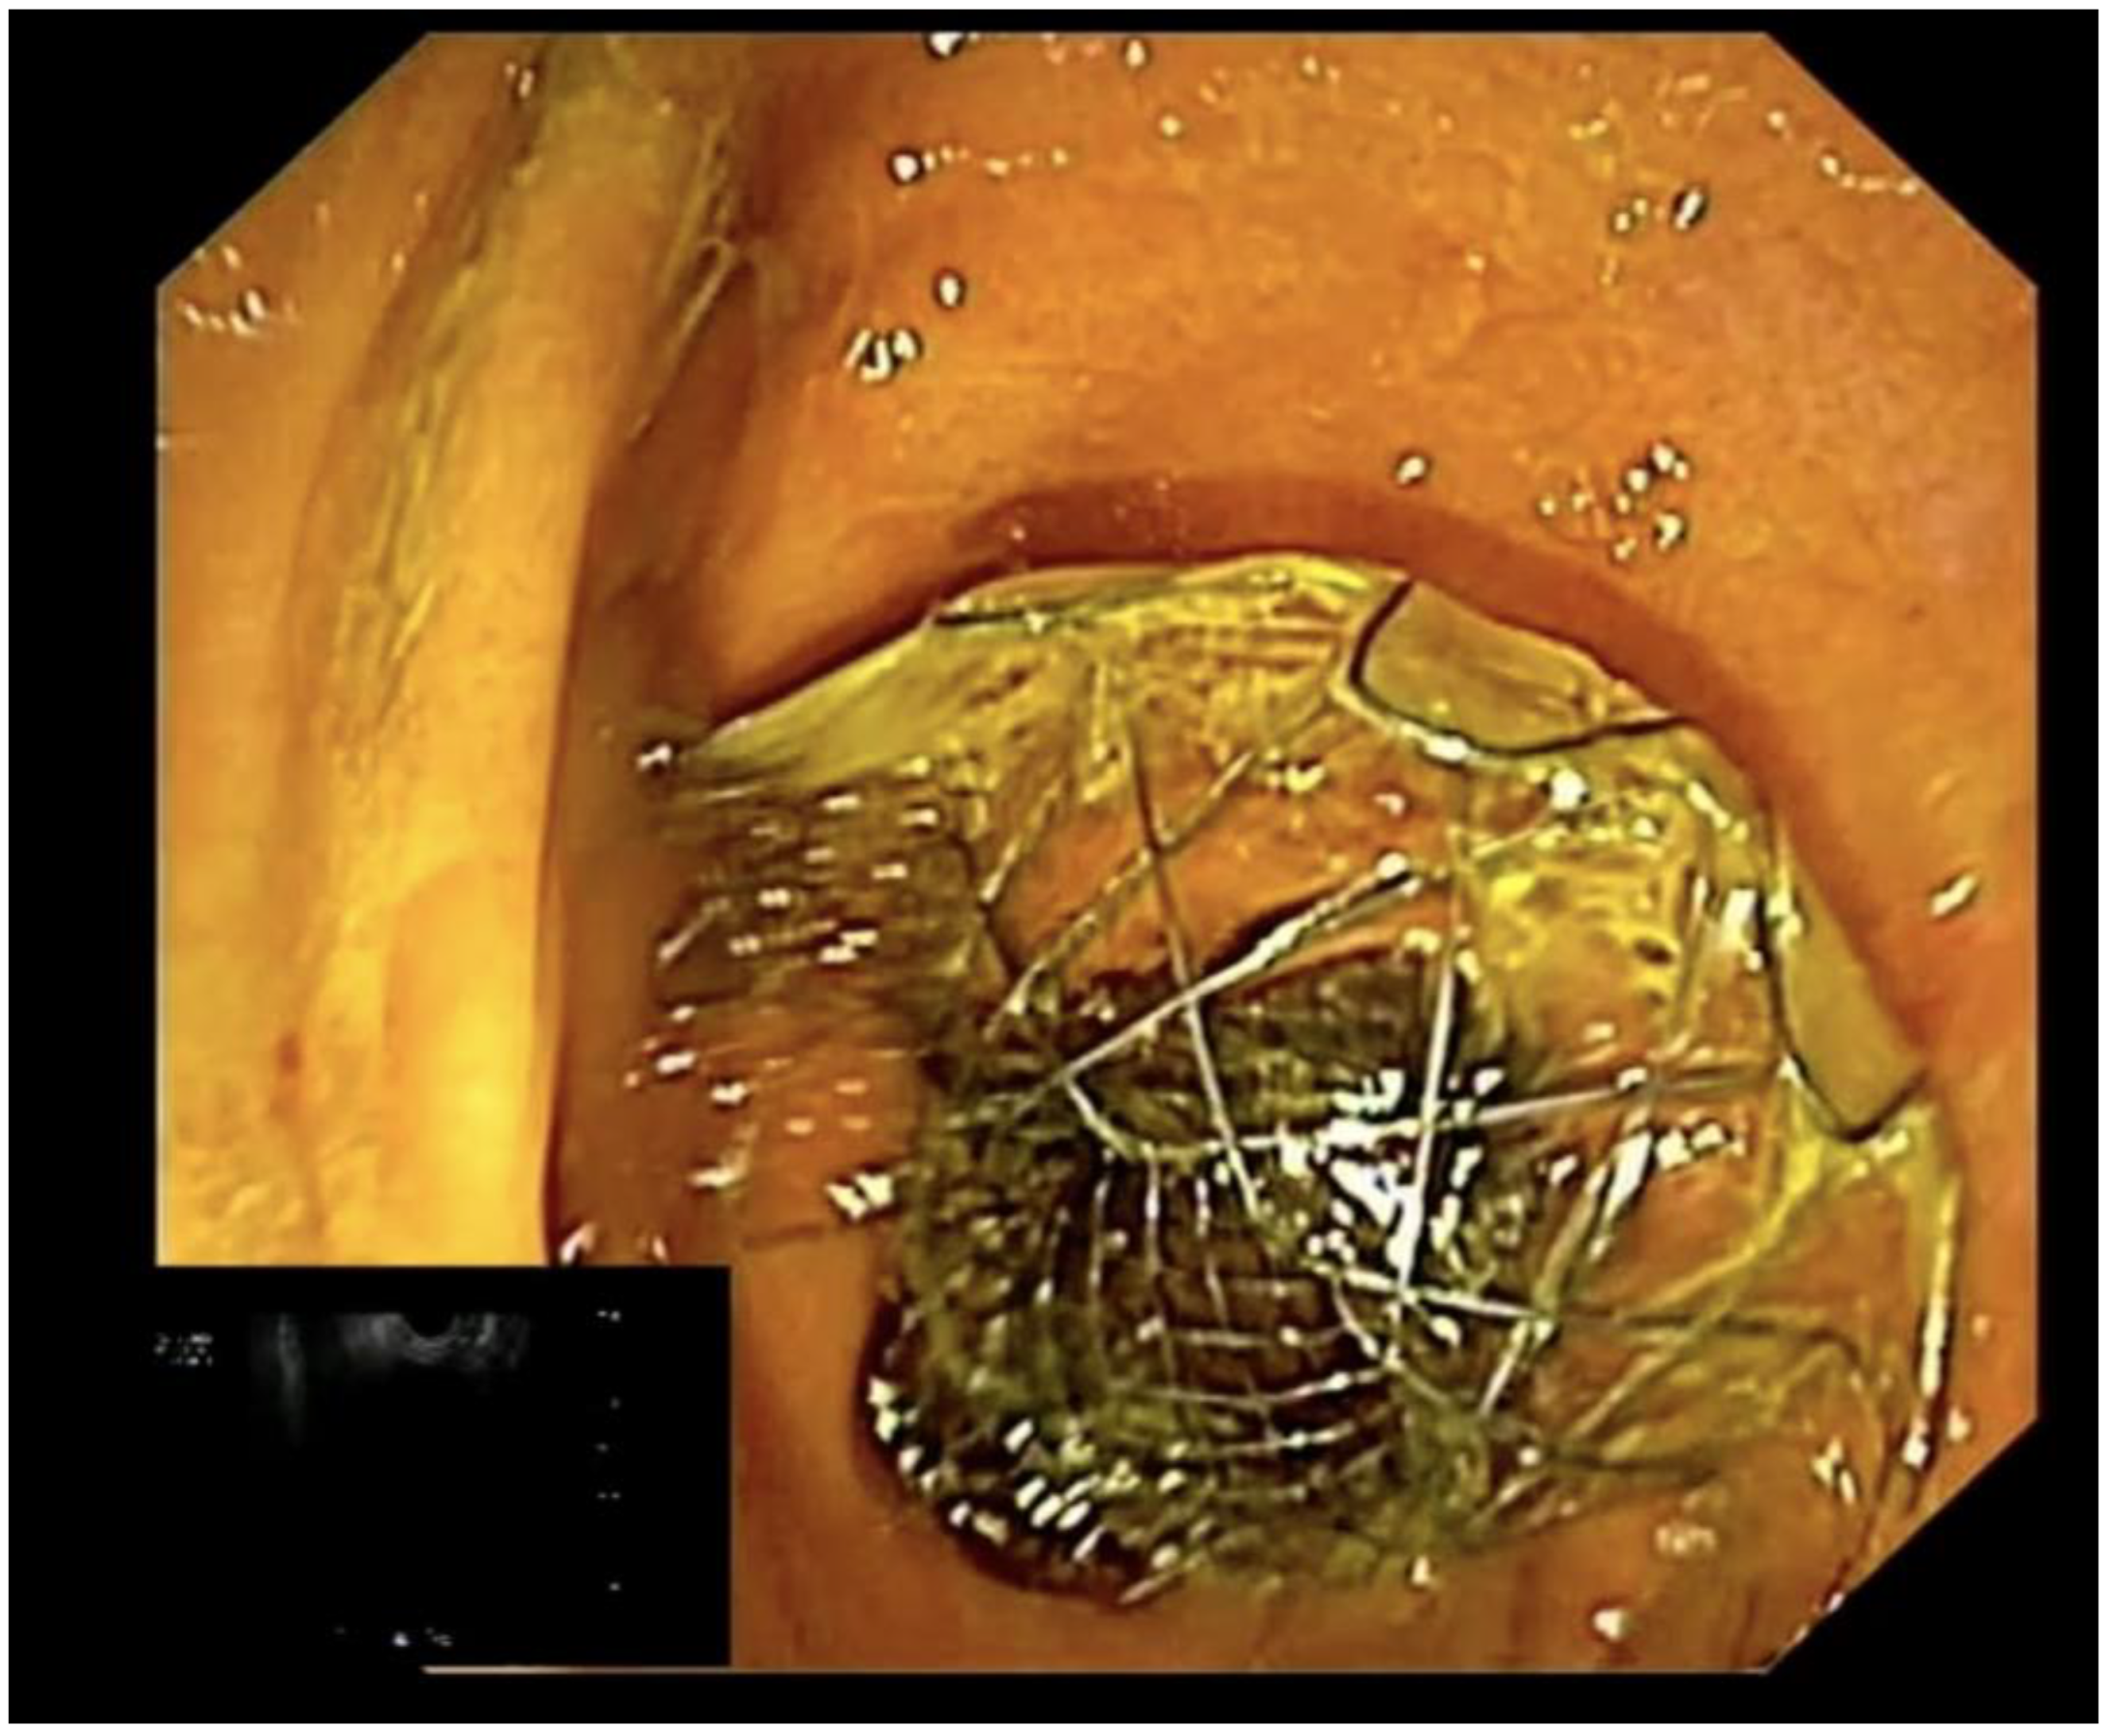

- Paduano, D.; Auriemma, F.; Spatola, F.; Lamonaca, L.; Repici, A.; Mangiavillano, B. Endoscopic ultrasound-guided choledochoduodenostomy with pyloric occlusion by proximal flange of electrocautery-enhanced lumen-apposing metal stent: Solving a rare adverse event. Endoscopy 2022, 54, E918–E919. [Google Scholar] [CrossRef] [PubMed]

- Mangiavillano, B.; Auriemma, F.; Paduano, D.; Lamonaca, L.; Spatola, F.; Repici, A. How to solve misplacement of a lumen-apposing metal stent during cholecystogastrostomy: Immediately perform a second one! Endoscopy 2022, 54, E421–E422, Erratum in Endoscopy 2022, 54, C11. [Google Scholar] [CrossRef]